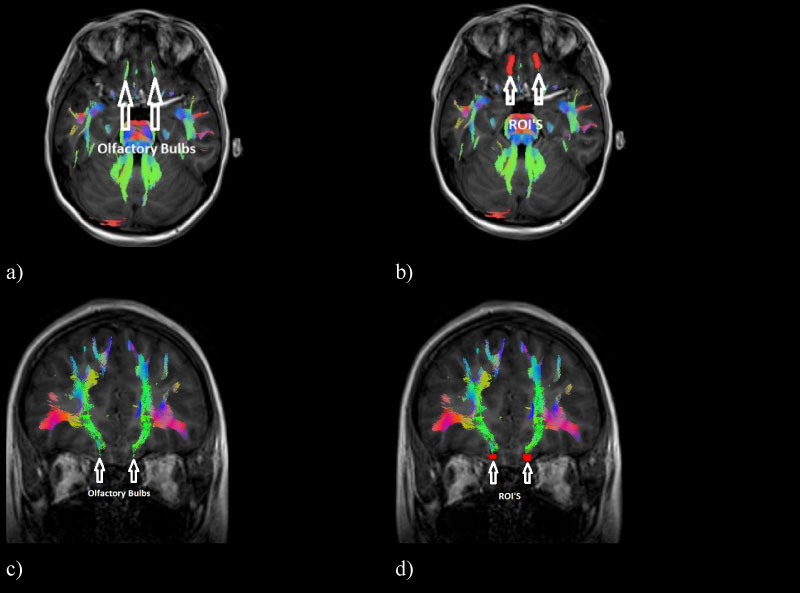

In this way, the olfactory path corresponding to the tracts of the olfactory bulbs, the olfactory cortex and the orbitofrontal cortex of the brain were characterized. The objective of being able to visualize the WM tracts in a 3D image is to be able to visualize the connectivity between the different brain zones corresponding to the olfactory system, in addition to representing an advantage for the doctor and their corresponding clinical interpretation. The measure of the diffusion parameters of the total tracts that the MedInria software provides (FA and ADC) were measured; these tracts can be seen in (Figure 2).

Figure 2: Olfactory pathway tracts containing the olfactory bulbs, the olfactory cortex and the orbitofrontal cortex of the brain, a) Left sagittal view, b) Posterior coronal view, c) Right sagittal view and d) Anterior coronal view. View Figure 2

In all the subjects, it was possible to reconstruct the WM tracts forming the olfactory pathway in a similar way.